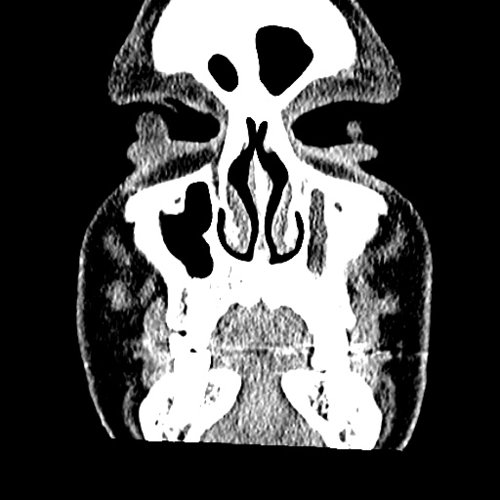

From www.embodi3d.com

Chronic sinusitis Dental, Orthodontic, Maxillofacial CTs Orthodontic Sinusitis Odontogenic sinusitis (ods) can present a therapeutic dilemma because multiple treatment strategies have been reported. Ods is distinct from rhinosinusitis in that it is. Sinusitis is an inflammation of the mucosal lining of the paranasal sinuses. It is actually inflammation of the maxillary sinus. Learn about the potential impact of orthodontic treatment on sinus issues, tips for preventing complications, and. Orthodontic Sinusitis.